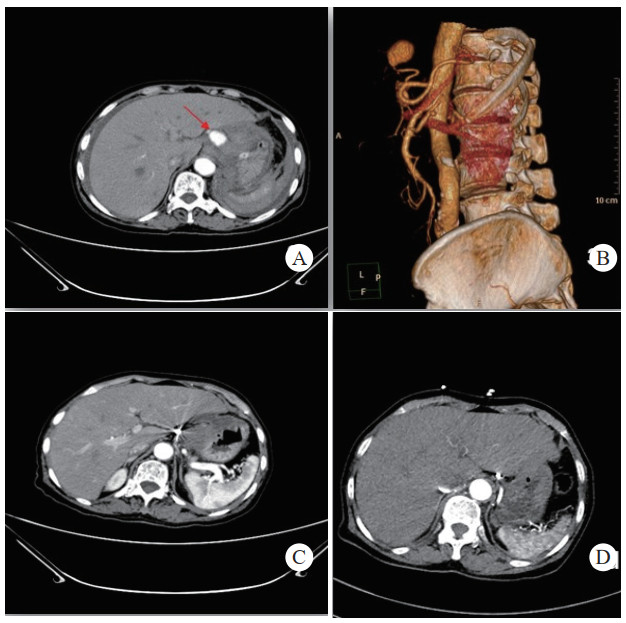

患者经介入栓塞治疗后,长期的随访CT及增强CT中,未出现责任动脉或瘤体再次发生破裂导致二次出血、弹簧圈移位及血栓异位栓塞等并发症,见图 3(病例3)。

| 注:A、B为患者术前CT增强扫描及血管重建技术,示胰腺炎影像,腹腔内见一血肿影,内可见与动脉强化一致的动脉瘤影像(箭头示),其供血动脉为胃左动脉;C为患者术后三天复查CT增强扫描,示血肿较前吸收减小,内见弹簧圈影及未见对比剂外溢。D为患者术后三年复查CT增强示,血肿消失,原动脉瘤处可见弹簧圈影及未见对比剂外溢 图 3 病例3术前、术后CT平扫及增强 |